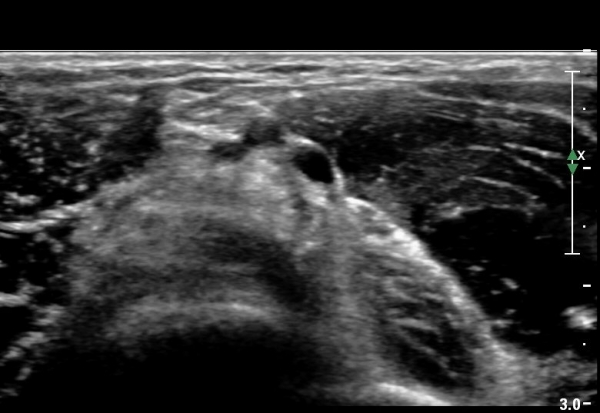

Á¶±Ý ´õ ¸»´ÜÀ¸·Î À̵¿ÇÏ¿© °üÂûÇÏ´Ï ÀÌµÎ¹Ú±Ù°Ç ½ÇÁú³» ÆÄ¿­°ú °üÀý ÁÖÀ§ ¼ö¾×Àú·ù°¡ °üÂûµÊ(±×¸² 4, 5).